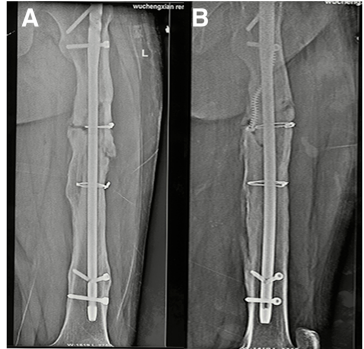

治疗「骨不连」,我们整理了 12 种方法!